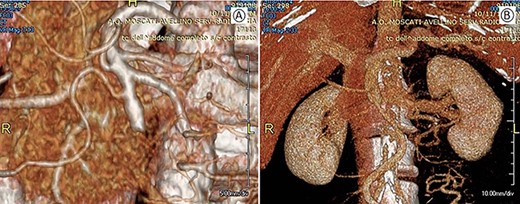

This case involved a 63-year-old man who had a history of hypertension, psoriasis and atherosclerosis. He referred the appearance of a light epigastric pain and general discomfort. Laboratory tests were normal. Abdominal ultrasonography was negative as well as the esophagogastroduodenoscopy and colonoscopy. Abdominal computer tomography (CT-scan) with contrast showed a solid mass of about 42 × 31 mm in the mesenteric adipose tissue, incorporating the distal part of the SMA and the superior mesenteric vein (SMV) (Fig. 1). A fluorodeoxyglucose positron imaging tomography/computed tomography (CT) showed an increased uptake (SUV 5.2) at the level of the mesenteric mass.

Preoperative CT; (A) arterial phase: the arrow shows the neoplastic mass traversed by the superior mesenteric artery. (B) Venous phase: the arrow shows the neoplastic mass in contact with the superior mesenteric vein.

Postoperative CT with 3D vascular reconstruction; (A) arterial phase: superior mesenteric artery with its branches saved. (B) Venous phase: mesenteric-portal axis pervious.